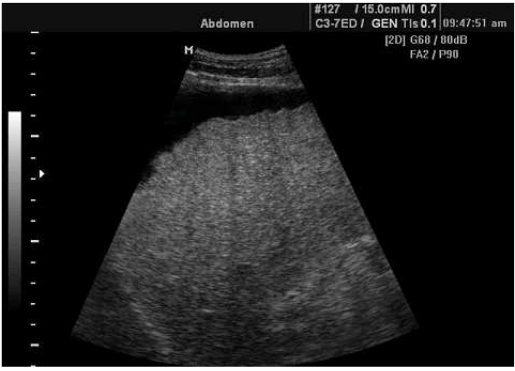

64.

一位50歲男性因為腹脹做腹部超音波檢查呈現如下圖,則下列敘述那一項最正確? (A)右側腎臟結石,合併輕微腎水腫(hydronephrosis) (B)肝臟呈現不均勻回音,合併腹水(ascites) (C)脾臟腫大,合併脾靜脈鼓脹(splenic vein engorgement) (D)胰臟發炎,合併胰管擴張(pancreatic duct dilatation)